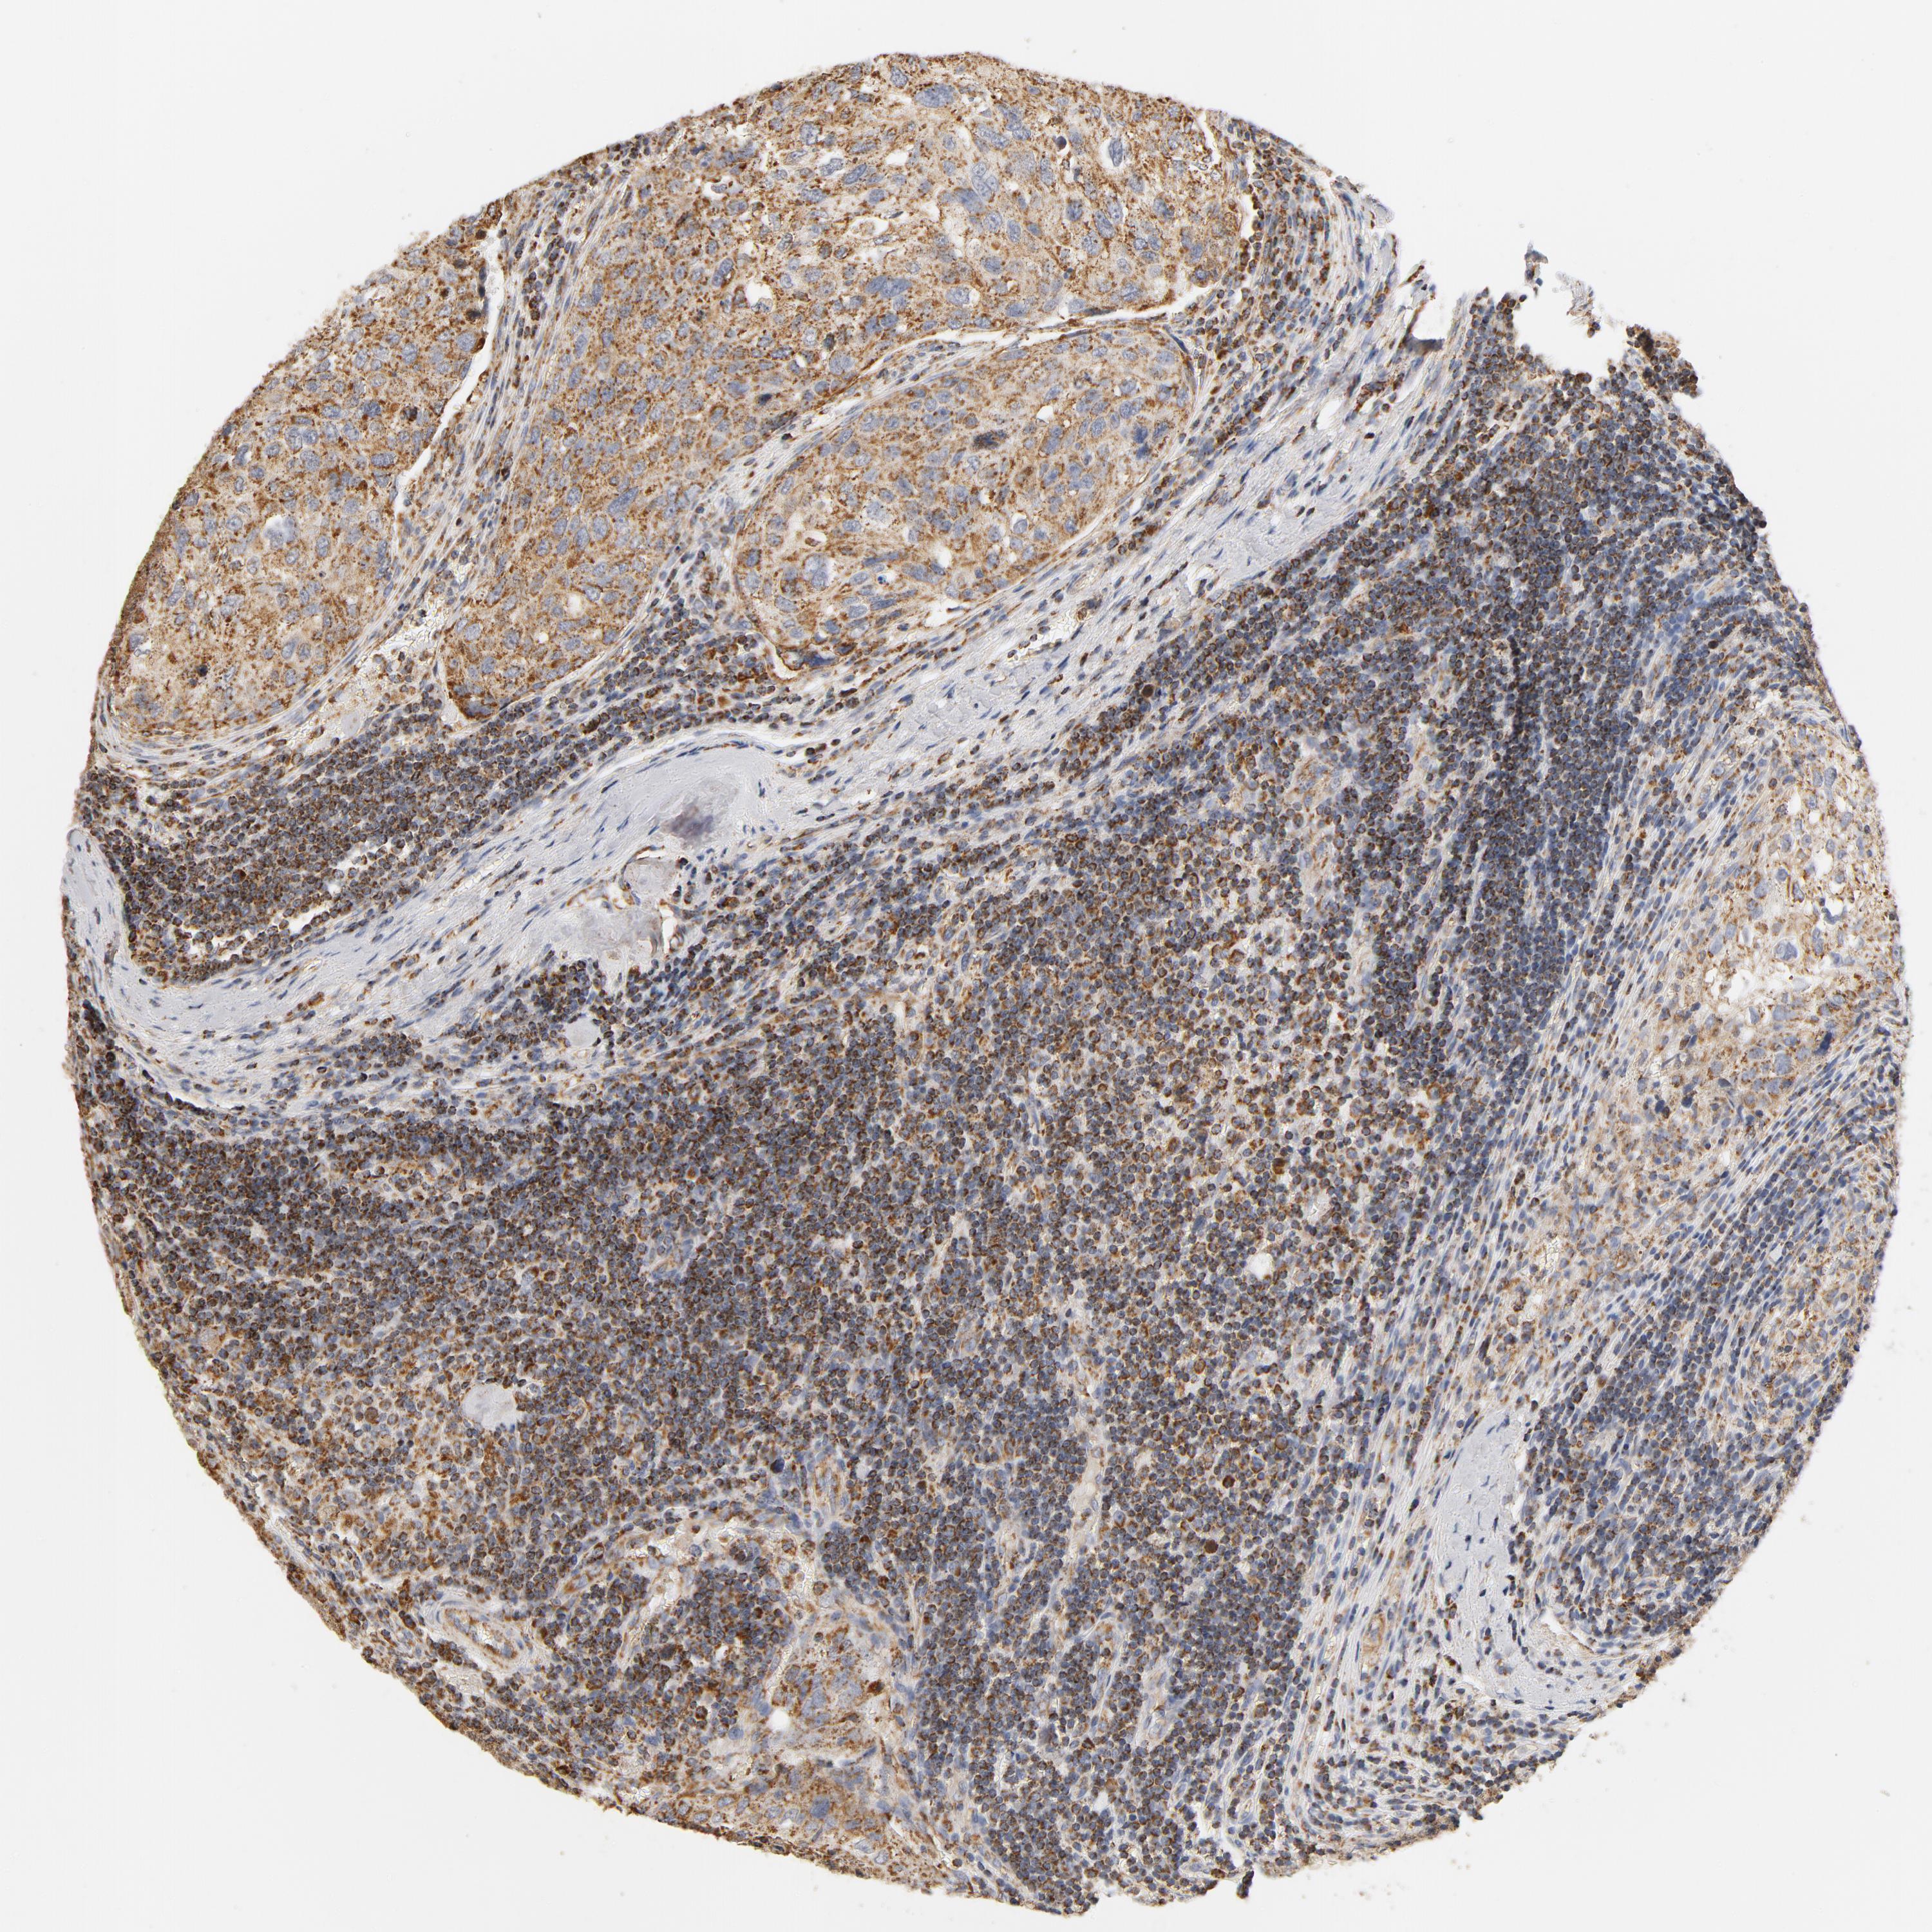

UROTHELIAL CANCER - Protein expressioni

A mouse-over function shows sample information and annotation data. Click on an image to view it in a full screen mode. Samples can be filtered based on level of antibody staining by selecting one or several of the following categories: high, medium, low and not detected. The assay and annotation is described here.

Note that samples used for immunohistochemistry by the Human Protein Atlas do not correspond to samples in the TCGA dataset.

Antibody stainingi

Antibody staining in the annotated cell types in the current human tissue is reported as not detected, low, medium, or high, based on conventional immunohistochemistry profiling in selected tissues. This score is based on the combination of the staining intensity and fraction of stained cells.

Each image is clickable and will lead to virtual microscopy that enables deeper exploration of all samples and also displays staining intensity scores, fraction scores and subcellular localization as well as patient and tissue information for each sample.

Antibody HPA002485

Antibody CAB004080

Staining

High

Medium

Low

Not detected

Intensity

Strong

Moderate

Weak

Negative

Quantity

>75%

75%-25%

<25%

None

Location

Nuclear

Cytoplasmic/membranous

Cytoplasmic/membranous,nuclear

Urothelial carcinoma, High grade

Urothelial carcinoma, Low grade